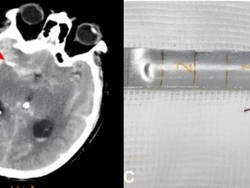

Pasutri Wajib Waspada! Dokter Bicara Risiko Sakit Kepala-Stroke Usai Bercinta

Pasutri wajib mewaspadai sakit kepala yang dapat muncul ketika berhubungan seks. Dokter juga mengingatkan risiko stroke yang mungkin terjadi setelah bercinta.